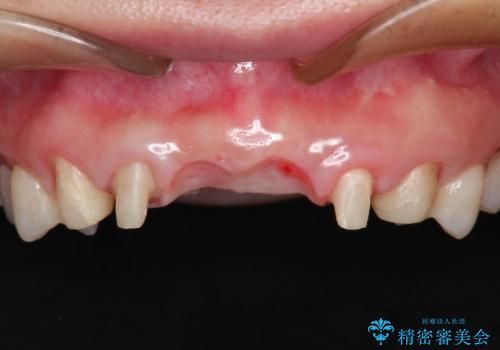

- 数ヶ月前に治療終了したブリッジの歯ぐきの違和感が強く、改善を求めて来院されました。

歯ぐきは著しく腫れ、少し触ると出血してしまうような状態であったためブリッジの再作製・歯周外科を用いた歯肉環境の改善を計画します。